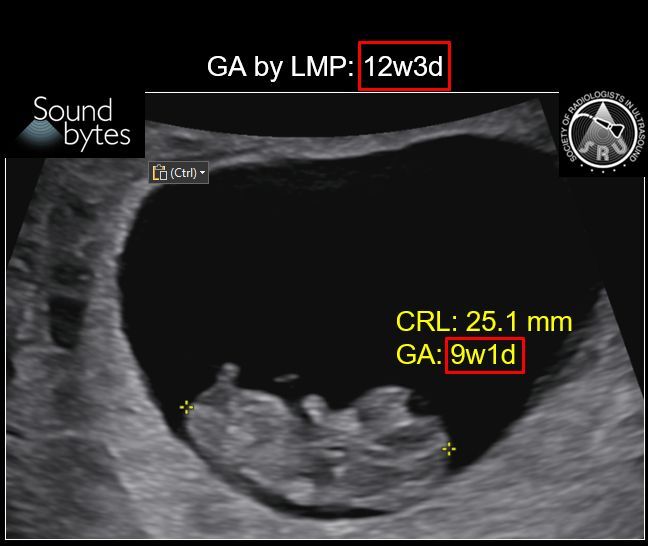

Answer: Size Date Mismatch Findings: Discrepancy of >7d in GA by LMP vs US late1st T (9 0/7 wk to 13 6/7 wk) suggests size-dates discrepancy, per ACOG guidelines (below). Case courtesy of Dr. April Griffith, U of UT #RadResidents #ultrasound #RadInTraining